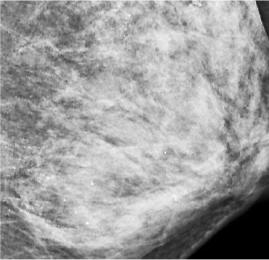

在X光片下,朱女士的乳腺里满是星星点点的钙化灶

武汉晚报讯(记者刘璇 通讯员谯玲玲 杨侠) 女子左侧乳房里发现数不清的细沙样钙化灶,在X光片上看着好像“满天星”。医生推测,极可能是她长期在外按摩保养乳房时用力过猛损伤乳腺所致。

最让医生意外的是她的左侧乳房。乳腺X线检查时,发现里面全部都是细小如沙子一样的钙化灶,布满整个乳腺。让管床医生陶龙犯难的是,如此多的细小钙化灶,无法判断哪些是良性哪些是恶性。

乳腺沙砾样钙化灶是乳癌的信号之一,需高度关注。为进一步确诊,朱女士接受了左侧乳腺核磁共振检查,没有发现大的异常,暂时排除了恶性的可能?!暗源τ诟呶W刺?。”陶龙再三叮嘱她,必须严密观察并定期复查,每3个月做一次乳腺彩超,一旦发现可疑病灶,及时手术治疗。

为寻找病因,陶龙详细询问了病史?!笆遣皇亲龉裁粗瘟??”面对医生的追问,朱女士一一否定,她告诉陶龙,自己一向注重保养,这些年一直在外面做精油推拿按摩,保养胸部。陶龙分析,极有可能是按摩师用力不当损伤了腺叶乳管,导致乳腺出现坏死性细小点状钙化。这种细小点状钙化,极易和癌症沙砾样钙化造成混淆,影响癌症的早期确诊。